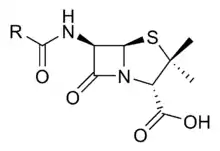

Les principaux antibiotiques ayant ce mode d'action correspondant à la famille appelée les Bêta-lactamines (pénicillines et céphalosporines)[7]. Ceux-ci agissent sur les enzymes de la machinerie de synthèse du peptidoglycane que l'on appelle pour cette raison les « protéines fixant la pénicilline » (penicillin binding proteins ou PBP).

Près de la moitié des antibiotiques utilisés en thérapeutique ciblent le ribosome bactérien et environ un quart d'entre eux sont des bêta-lactames, qui ciblent la synthèse de la paroi bactérienne. Si on regarde les prescriptions, on constate que ce sont les bêta-lactames (pénicillines et céphalosporines) qui sont les antibiotiques les plus utilisés, en particulier par les médecins généralistes. En France, ils représentent près des deux tiers des doses définies journalières utilisés, devant les macrolides (~15 %)[9].

De nombreuses souches résistantes fabriquent une enzyme qui modifie ou qui clive la molécule d'antibiotique, la rendant inactive. C'est le mécanisme principal de résistance aux β-lactamines (famille de la pénicilline et des céphalosporines) qui implique les enzymes de la famille des β-lactamases.